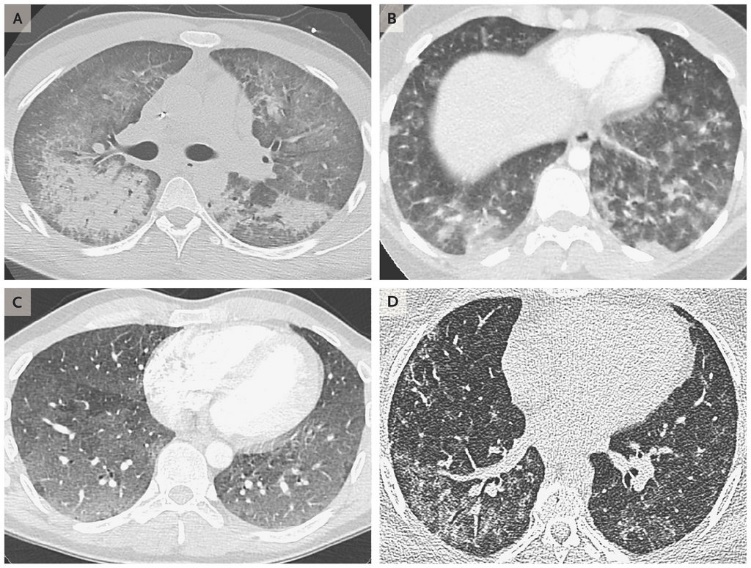

Thống kê của Bộ Y tế và Dịch vụ Nhân sinh Mỹ cho hay, khoảng 1.100 trường hợp gần đây mắc bệnh phổi cấp tính xuất hiện ở những bệnh nhân đều có tiền sử hút thuốc lá điện tử với độ tuổi từ 14 đến 69. Riêng New York đã có tới 110 trường hợp. Đây là lời cảnh tỉnh cho các bậc phụ huynh về việc bùng nổ tỷ lệ sử dụng thuốc lá điện tử ở thanh thiếu niên có thể dẫn đến tử vong.

Khi sử dụng, thiết bị chuyển một lượng tinh dầu chứa nicotine lỏng trong buồng đốt thành dạng hơi nước hay sương mù để người dùng hít vào. Trong một liều có chứa các hạt siêu mịn đi sâu vào phổi, nhiều trong số các hạt này chứa lượng hóa chất độc hại liên quan đến ung thư, bệnh hô hấp và tim mạch như nicotine, kim loại nặng như niken, thiếc và chì.